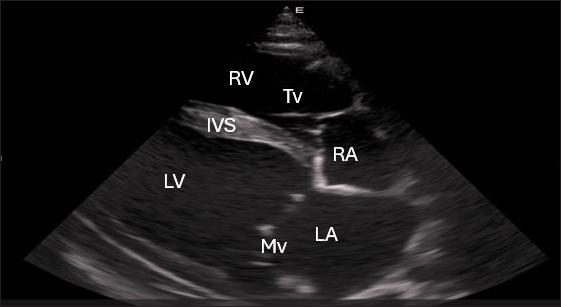

Right parasternal ultrasonography

By positioning the probe perpendicularly in the fourth intercostal space or longitudinally in the fifth space with a little clockwise rotation, the interventricular septum, ventricles, and atria could be observed in the caudal long-axis four-chamber view (Fig. 1). From this vantage point, all camels could be seen to have a left ventricle, mitral valve, interventricular septum, right ventricle, and tricuspid valve. Figure 2 shows that in the short-axis image of the cardiac ventricles obtained with a little clockwise rotation at the 4th ICS, only the right ventricle, interventricular septum, and left ventricle were visible. Here, the dimensions of all camel heart were measured in M mode. The right parasternal two-dimensional short-axis pictures of the heart’s base in the first frame were used to determine the LA/Ao ratio, by applying 2D and M mode (Figs. 3 and 4). Despite some difficulties, we successfully acquired a pulmonary image by attempting to acquire the right ventricular outflow tract for the right short axis at the level of the great vessels.

Fig. 1. Right parasternal longitudinal axis (systole) of 16 years racing camel showing Lv=left ventricle, Rv=right ventricle, Ivs=Inte3r ventricular septum, Mv=mitral valve, and Tv=tricuspid valve.